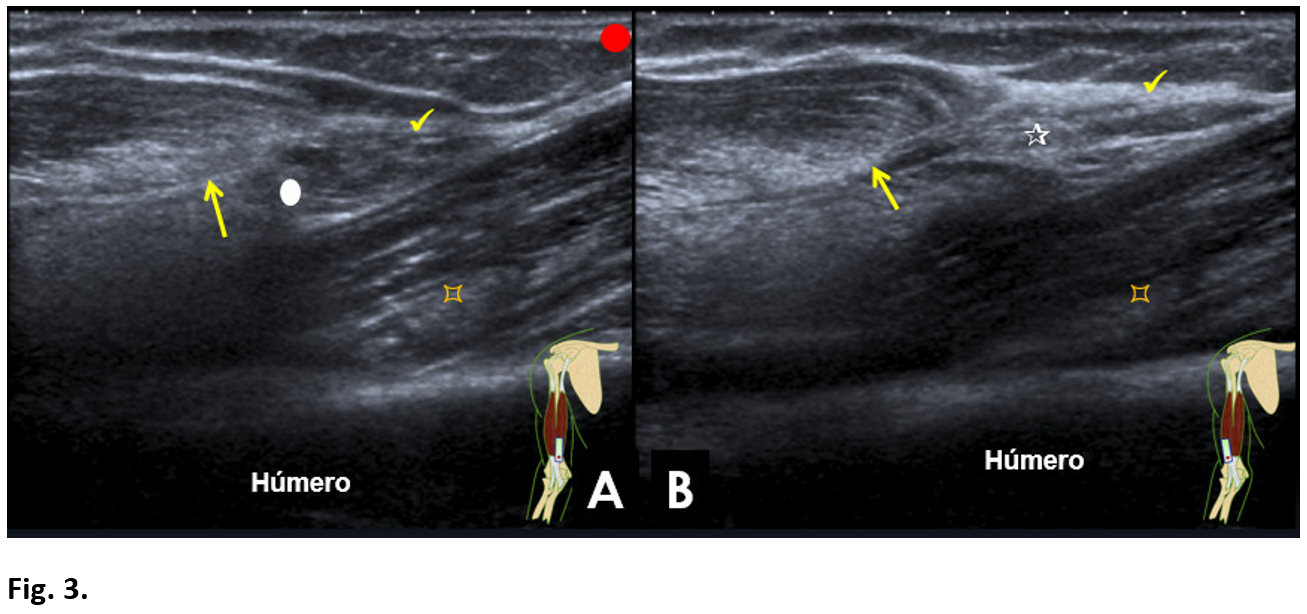

The biceps brachii is a muscle primarily supinator and secondarily flexor of the elbow. The distal tendon of the biceps is a flat tendon, which forms about 7 cm cranial to the elbow joint, from a central tendinous septum from the medial and lateral heads (Fig. 1). Once formed, superficial to the brachialis muscle, it has an oblique path from medial to lateral, and is directed in depth towards its insertion in the radial tuberosity. At the same time, it rotates 90º on its axis, so that its anterior face, faces laterally in its distal segment. Biomechanical studies have shown that the fibers of the short portion are inserted more distally in the bicipital tuberosity and contribute mainly to the flexion of the elbow and the long portion the fibres’ are inserted more proximally and they assist in supination of the forearm (1). The bicipital aponeurosis, originates, at the level of the distal myotendinous junction, of the most ventral and medial zone, crosses over the tendon and joins the superficial fascia of the forearm in the ulnar region (1,2).

Axial section:

Long head (white circle). Short head (white triangle). Central tendinous septum (arrow). Bicipital aponeurosis (tick). Anterior brachial muscle (pointed square).

Longitudinal section:

Bicipital aponeurosis (tick). Central septum of the biceps tendon (arrow). Anterior brachial muscle (pointed square).